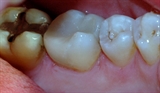

![]()

Bruddlinjen førte over tid til at tannen frakturerte.

Den gjenstående amalgamfyllingen ble fjernet, og tannen ble bygget opp igjen med en plastfylling.